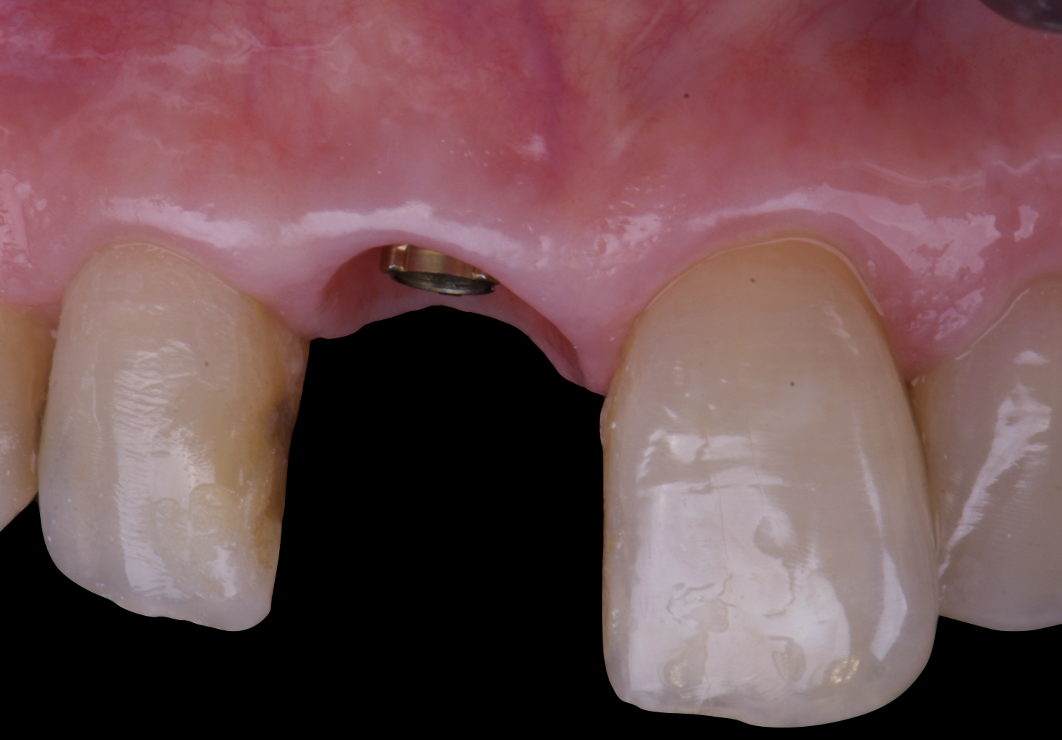

The surgical protocol began with the atraumatic extraction of tooth 1.1 to preserve as much of the alveolar socket as possible. Immediately following extraction, an N1 implant was placed into the socket using a guided surgical approach to ensure ideal three-dimensional positioning. The “one abutment one time” technique was applied to minimize soft tissue manipulation during the healing phase, which is particularly important in esthetic areas.

Given the significant buccal defect, guided bone regeneration (GBR) was performed simultaneously. A mixture of autologous bone and creos™ xenogain™ was applied to the defect and covered with a resorbable creos™ membrane to restore ridge width and support the buccal contour. In addition, a connective tissue graft was harvested and placed in the vestibular region to increase the thickness of keratinized mucosa. This combined approach addressed both hard and soft tissue deficiencies, providing the biological foundation for a stable and esthetic outcome.